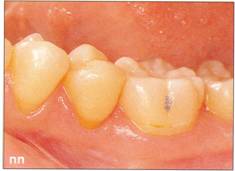

Fi 545e45f g 5-71 Three months after transplanta. tion. Notice the dark appearance of the crown. |

Fi 545e45f g 5-7m After bleaching of the transplant. ed tooth. |

Fi 545e45f gs 5-7n and 5-70 Composite resin res. toration of the transplanted tooth. |

Fi 545e45f g 5-7p Fi 545e45f ve months after transplantation. |

Fi 545e45f g 5-7q Three years after transplantation. |